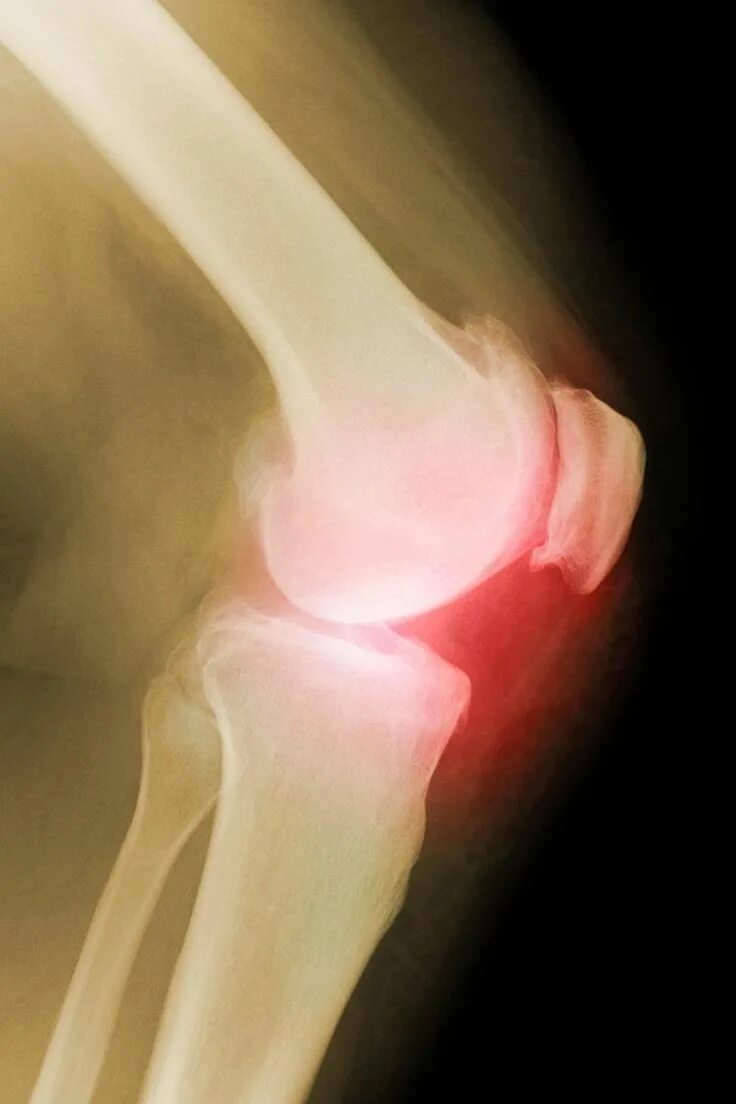

Болезнь соли в суставах